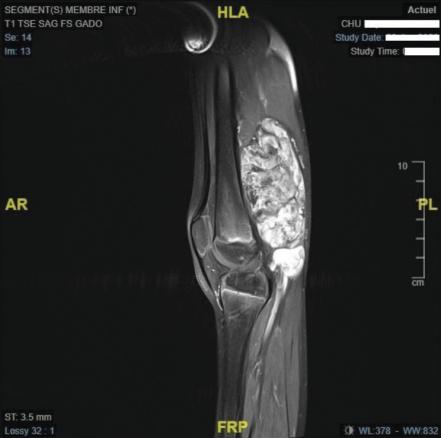

L’IRM confirme l’existence d’une masse tissulaire avec contingent graisseux refoulant les structures de voisinage (figures ).

L’IRM confirme l’existence d’une masse tissulaire avec contingent graisseux refoulant les structures de voisinage (

L’IRM est l’examen d’imagerie de choix pour préciser la localisation et les rapports de la lésion. Si elles sont réalisées, la radiographie ne montre pas de lyse osseuse et l’échographie met en évidence une masse hétérogène à contenu graisseux.